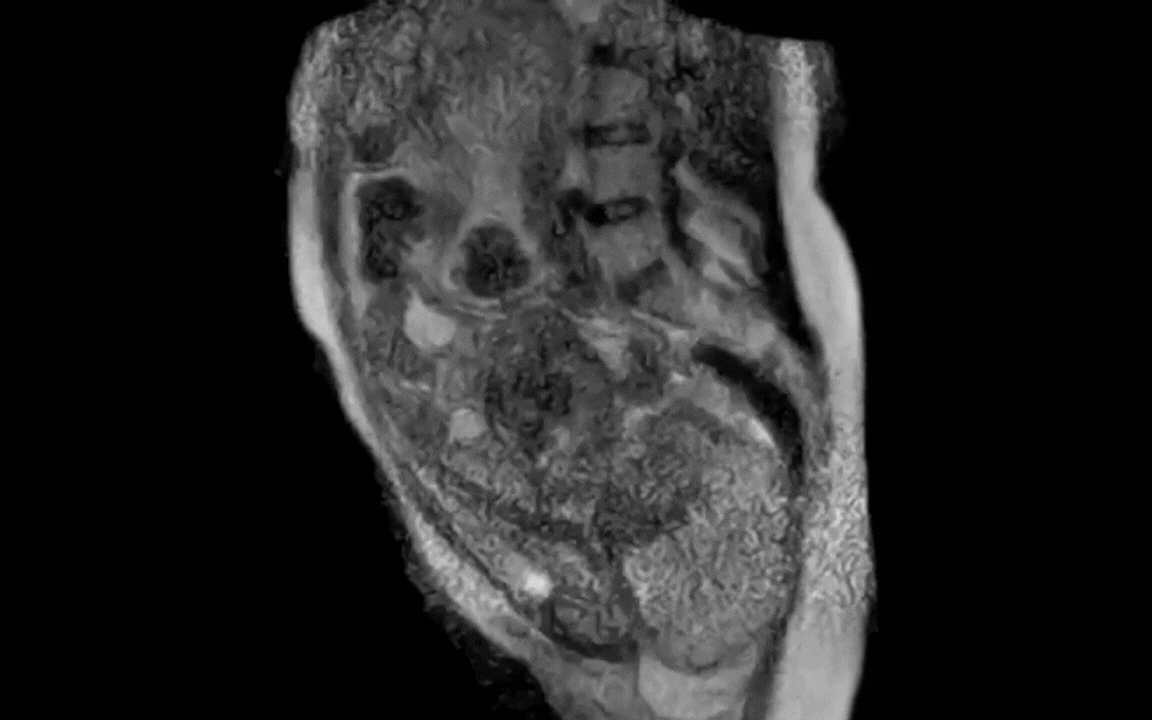

Quay lại với ca sinh nở, các nhà khoa học tại Bệnh viện Đại học Charité, Berlin, Đức đã ghi lại 45 phút cuối của quá trình chuyển dạ , sau đó rút gọn thành một đoạn video dài 25 giây. Hình ảnh cho thấy rõ vị trí thai nhi, sự di chuyển của em bé qua ống sinh và sự thay đổi của các cơ quan trong cơ thể người mẹ khi rặn sinh.

Theo nhóm nghiên cứu, trước đó hiểu biết về cơ chế sinh nở chủ yếu dựa trên giả định và các nghiên cứu X-quang đã cũ. Việc quan sát trực tiếp bằng MRI giúp bác sĩ hiểu rõ hơn quá trình này, đặc biệt hữu ích trong những ca sinh khó.